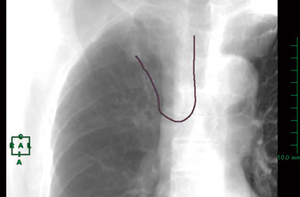

図1 オブリークMPR

二股に分かれた気管支のうち一方が病変外に通り抜けている。内側の気管支(↓)が生検に適していると特定した。

病変に入り込む気管支をオブリークMPRで詳細に分析すると,さまざまな走行を呈していることがわかった。病変の中で蛇行していたり,急に細く変化したり,二股に分かれたうちの一方が病変外に通り抜けていたり(図1),また,生検に適する気管支が1本に限られていたり,まったく気管支が入っていないといった,困難が予測されるケースも見受けられた。